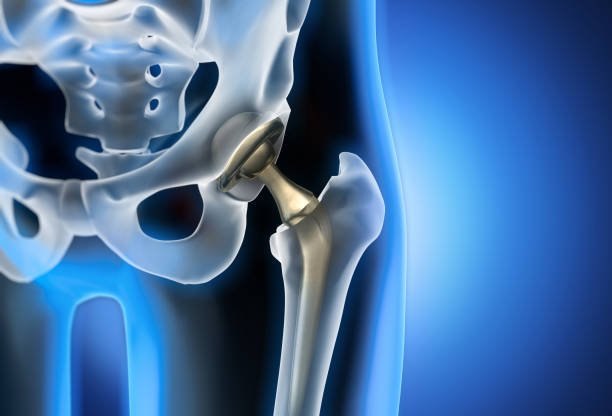

Hip Replacement — also called Total Hip Replacement (THR) or Hip Arthroplasty — is a surgical procedure where a damaged or diseased hip joint is replaced with an artificial implant made of metal, ceramic, or high-grade plastic. The goal is to relieve pain, restore mobility, and improve overall quality of life.

It’s most commonly recommended when severe arthritis, injury, or degeneration makes daily activities like walking, climbing stairs, or even sitting painful and difficult.